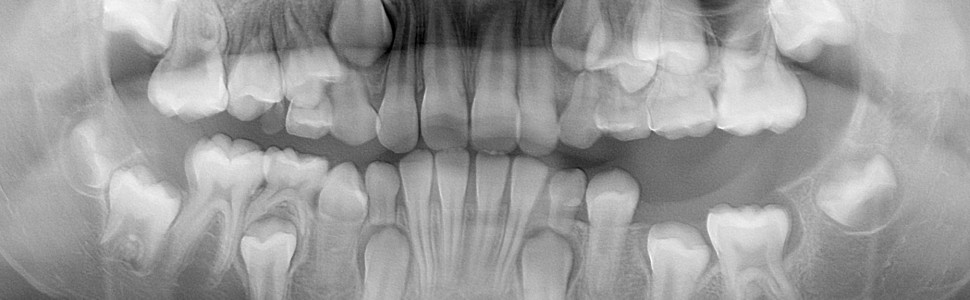

Artykuł przedstawia przykład malformacji rozwojowej, jaką jest zębiak. Ten problem kliniczny najczęściej dotyczy dzieci. Zębiak bywa przyczyną zatrzymania okolicznych zębów i dlatego często wykrywa się go dopiero w momencie, gdy ząb stały nie pojawia się w łuku zębowym po okresie fizjologicznej wymiany. Charakterystyczny obraz radiologiczny zębiaka nie nastręcza trudności w jego rozpoznaniu.

The article presents an example of a developmental malformation such as the odontoma. In most cases, the clinical problem affects children. The odontoma can cause the retention of surrounding teeth. For this reason, it is often   detected when the permanent tooth does not develop in the dental arch after the period of physiological change. The diagnosis can be estabilished without any difficulty due to the characteristic radiological picture.